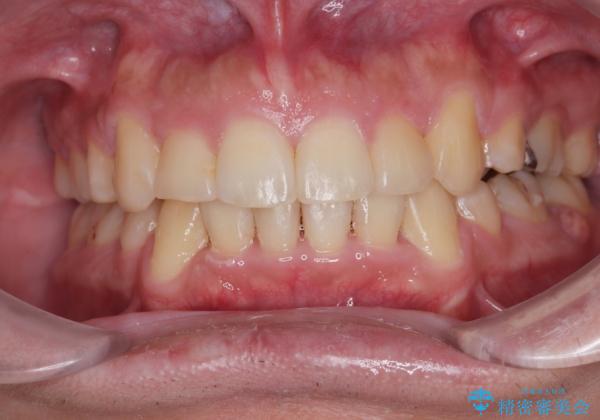

右上第一小臼歯は歯根癒着により移動せず、左上第二小臼歯は移動はするものの非常に動きが鈍かったため、抜歯したスペースを閉じるまでに非常に時間がかかってしまいました。

患者様には辛抱強く治療にお付き合いいただき、すっきりとした口元に仕上げることができました。